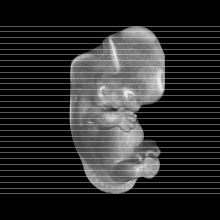

Carnegie Stage 20 (50 post-ovulatory days)

Most embryos at stage 20 are approximately 50-51 postovulatory days old and measure 21-23 mm in length. Distinguishing criteria for this stage include upper limbs slightly bent at the elbows, short stubby fingers, hands curving over the cardiac region but still far apart from each other, and a fringe-like vascular plexus that marks growth centers laterally in the superficial tissues of the head.

Animations

MRI Slice Selector